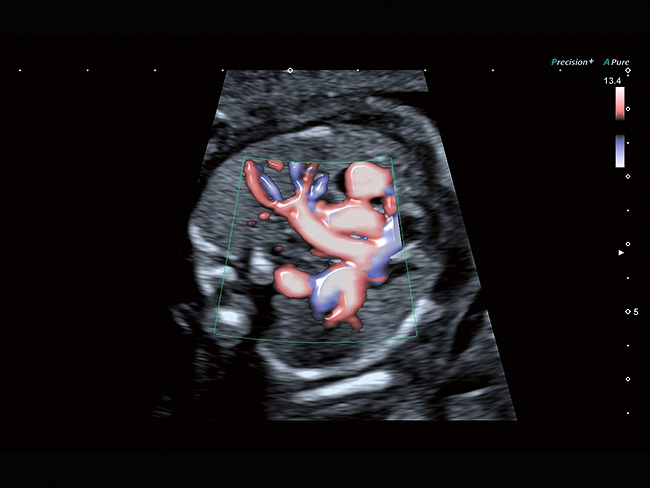

• расширенный динамический поток (ADF),

Aplio a550 может работать с линейным матричным датчиком и поддерживает новейшие монокристаллические датчики. Также Aplio a550 поддерживает большое количество дополнительных опций, таких как - SMI, Компрессионная эластография, Эластография сдвижной волны, Smart Fusion, исследования с использованием контраста (CEUS), 3D реконструкции в реальном времени (4D), функции автоматической оценки подвижности миокарда и фракции выброса.

Трехмерная реконструкция ЦДК:

Да

Энергетический допплер:

Цветовой допплер: